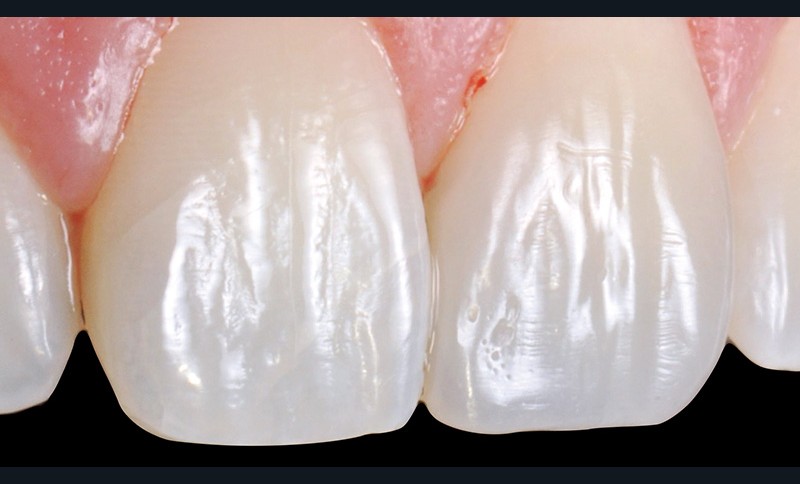

7. Un premier dessin est apporté à la fraise flamme bague rouge pour marquer les concavités et imiter les stries horizontales de croissance (périkématies). Puis le polissage est effectué à l’aide d’une pointe Identoflex® jaune (Kerr). Le brillantage est ensuite assuré par une cupule cloche Identoflex® grise (Kerr).

8. Sur cette vue de face, on se rend bien compte que la 21 est…